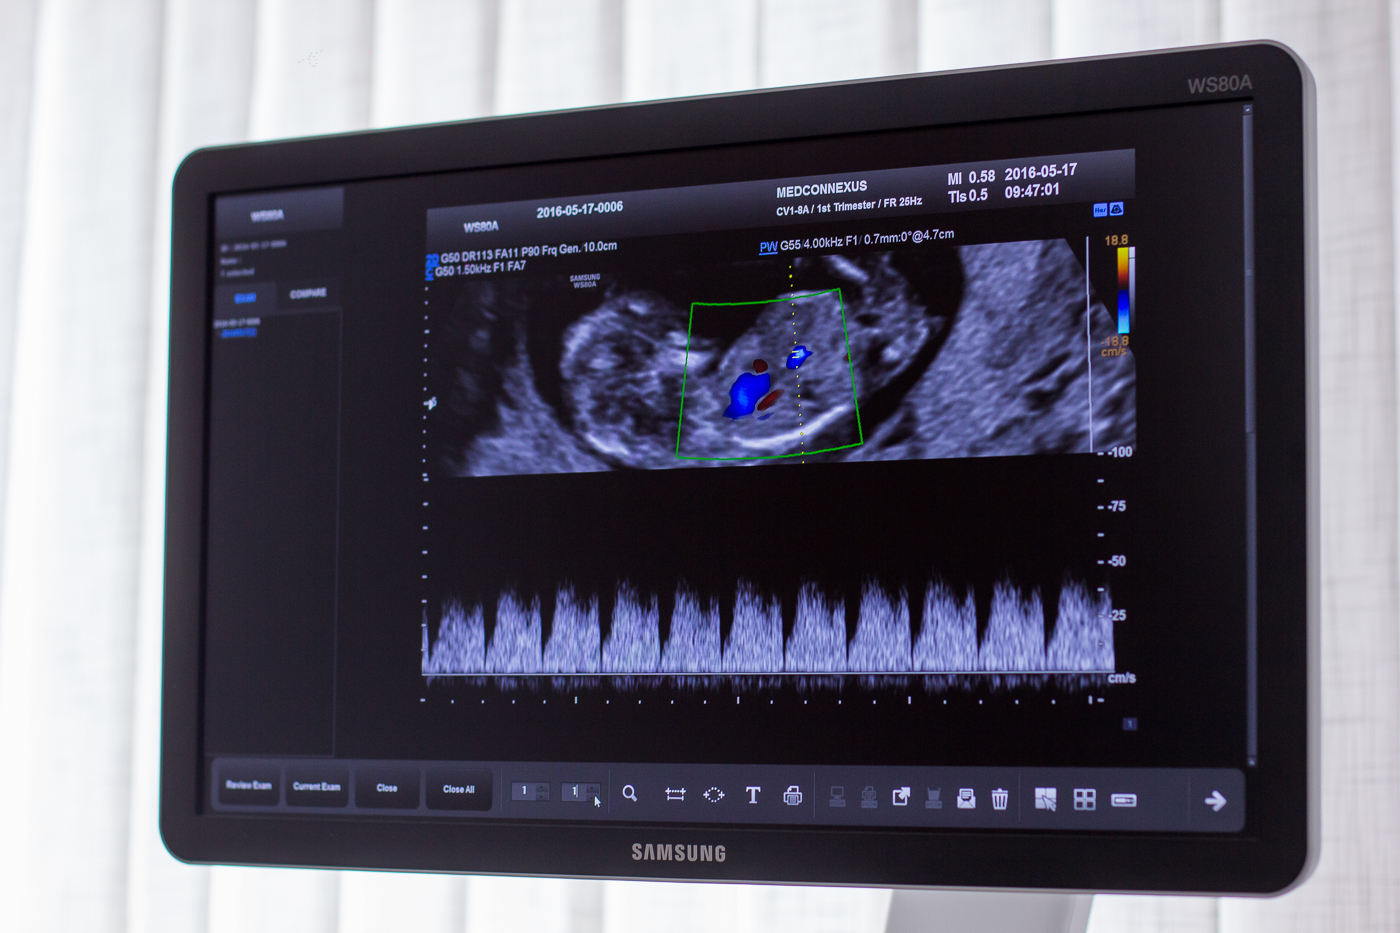

A Medconnexus Gyógyászati Központban kiemelt szerep jut a terhesgondozásnak, azon belül is a magzat fejlődésének rendszeres ultrahangvizsgálatokkal történő ellenőrzésének. Célkitűzésünk, hogy mind az édesanya, mind pedig a magzat egészségét szorosan obszerválva kísérjük végig a terhességet családtervezési tanácsadástól egészen a szülésig. A terhesgondozás elengedhetetlen elemeként a terhesség első igazolásától az egész terhesség során nyomon követjük ultrahanggal a magzat és a méhlepény méhen belüli elhelyezkedését, fejlődését. A magzati fejlődés és állapot diagnosztikájának részeként flowmetriás (áramlás-diagnosztikai) és CTG vizsgálatokat végzünk.

A vizsgálati protokolloknak megfelelő időpontokban elvégezzük a szükséges paraméterek mérését, mint például a tarkótáji bőrredő, az orrcsont, vagy a magzati vesék mérését. Az 5 dimenziós felvételekkel családi eseménnyé emeljük a várandósok gondozását.